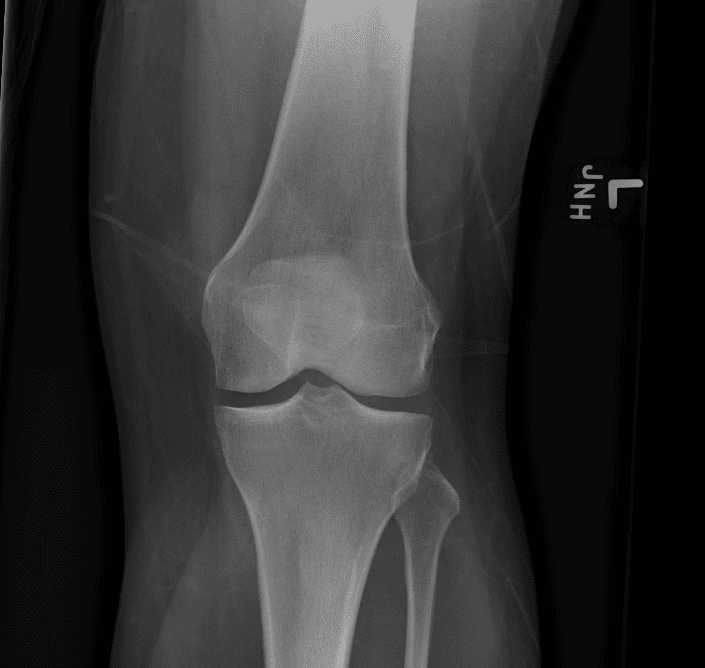

Simula o plantão incluindo casos sutis ou difíceis e alguns normais.